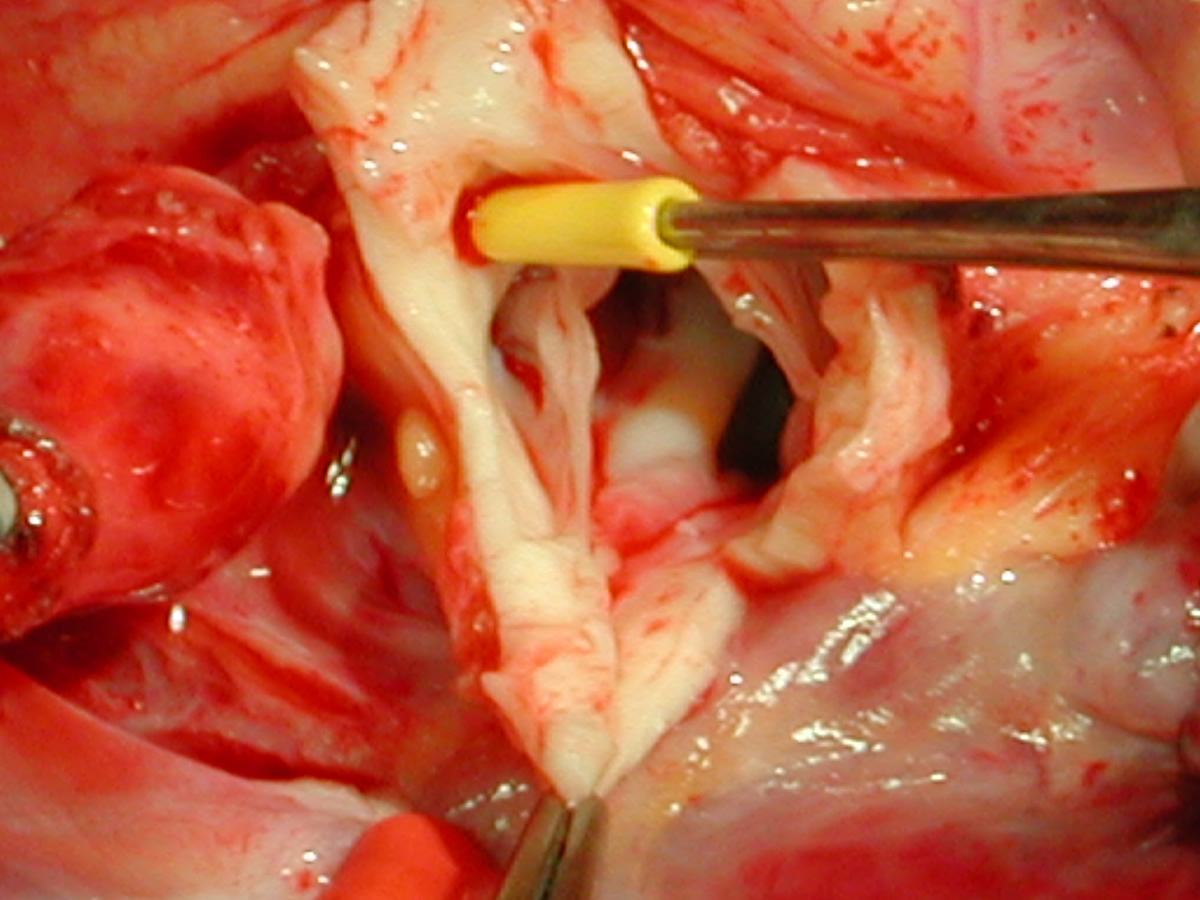

The operative approach is through a median sternotomy with the use of cardiopulmonary bypass and bicaval venous cannulation. The first dose of cold blood cardioplegia is antegrade; the remaining doses are retrograde.

High ascending aortic cannulation adjacent to the innominate artery for maximum exposure of the ascending aorta and to allow length for positioning of the patch in the ascending aorta.

One dose of antegrade cardioplegia followed by retrograde cardioplegia.

Pulmonary homograft or pericardial patches (tanned in glutaraldehyde) for the “shields”. These patches should not be too large – this will lead to aortic insufficiency.

First coronary sinus incision in noncoronary sinus to facilitate exposure of the incisions into the coronary orifice sinuses.

In most cases, the right coronary artery sinus should be opened to the left of the coronary orifice and the left coronary artery sinus to the right of the coronary orifice. Occasionally one may not have enough room between a coronary orifice and the aortic valve; in this case the incision site should be tailored to the situation.

Ensure similar orifice sizes between the proximal and distal ascending aorta after patch augmentation by the use of a sizing dilator.

Transesophageal echocardiography to assess completeness of repair, coronary blood flow postoperatively, wall motion abnormalities, and adequacy of aortic valve.